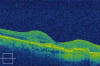

Paciente previamente diagnosticada de DMAE atrófica en ambos ojos que acude a nuestra consulta para valoración presentando una agudeza visual de 0,05 en el ojo derecho y de 0,86 en ojos izquierdo. En el fondo de ojo se observa maculopatía atrófica en ambos ojos con restos de sangre en el ojo derecho perifoveal. En la imagen OCT se observa la clara diferencia en definición de imagen con respecto al fluido subretiniano del Stratus (fig. 7) en comparación con el Cirrus (fig. 8) y la escala de colores utilizada por éste (fig. 9).

Fig. 8: Fluido subretiniano subfoveal por membrana neovascular visto por el

Cirrus.